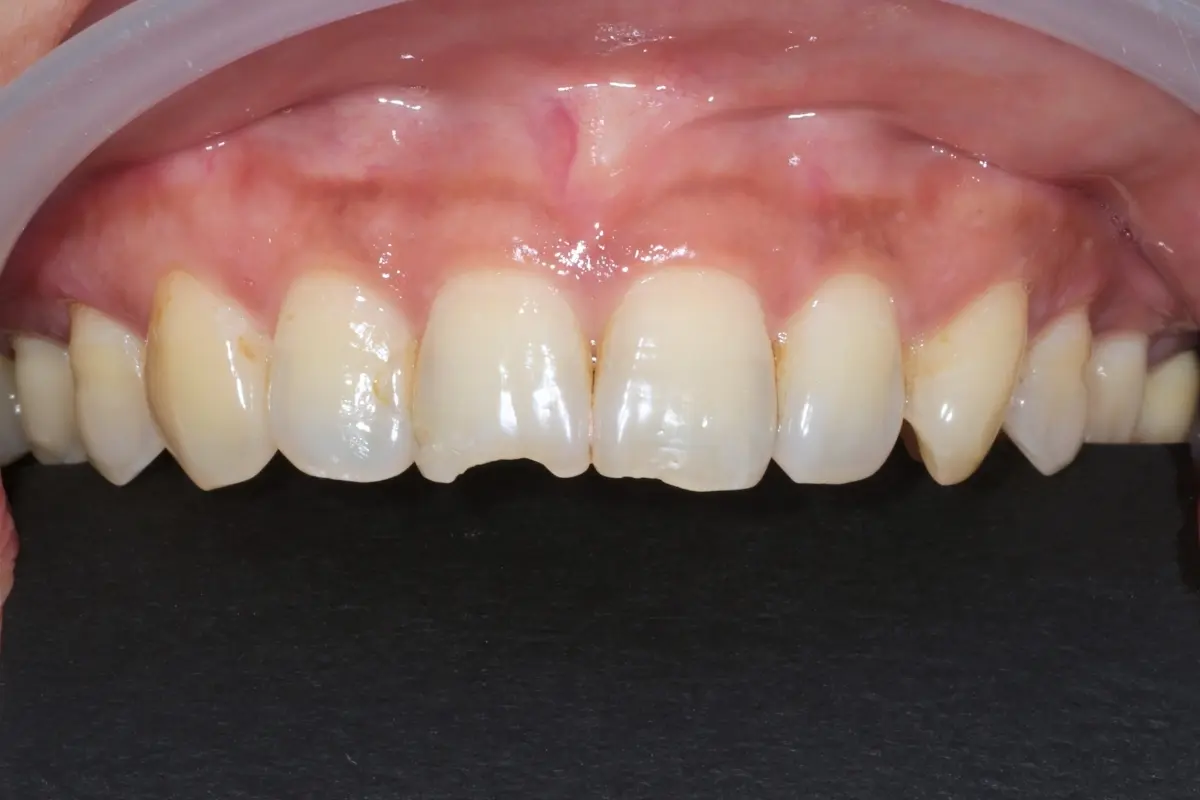

Dentist 陳昕 全口照護醫師 看診項目 前牙美學仿生樹脂補牙/全科牙醫 學經歷 臺北醫學大學牙醫系學士 前天主教新店耕莘醫院醫師 前臺北榮民總醫院醫師 亞洲齒列再生研究學會Advance植牙補綴專科訓練 微光私塾牙周雷射微創治療技術訓練 臺灣牙醫顯微美學治療學會會員醫師 中華審美牙醫學會會員醫師 CASE 案例分享 滲透型樹脂修復 主治醫師 陳昕 治療時間 單次療程 主訴 想處理前牙白白的色斑 前牙美學/仿生美學樹脂 主治醫師 陳昕 治療時間 單次療程 主訴 牙齒整齊,但門牙中間縫隙明顯,影響笑容美觀 前牙美學/陶瓷貼片 主治醫師 陳昕 治療時間 約1個月 主訴 兩顆門牙缺角,想要重建外觀 前牙美學/滲透型樹脂修復 主治醫師 陳昕 治療時間 單次療程 主訴 門牙有長期存在的白斑與表面不平整,影響外觀與自信 前牙美學/仿生美學樹脂 主治醫師 陳昕 治療時間 約兩週 主訴 矯正後的黑三角縫問題 前牙美學/仿生美學樹脂 主治醫師 陳昕 治療時間 約三週 主訴 因牙周病產生的黑三角縫 前牙美學/牙冠增長術、仿生全瓷牙冠 主治醫師 陳昕 治療時間 約6個月 主訴 牙齒排列不整、假牙外觀不自然 前牙美學/仿生美學樹脂 主治醫師 陳昕 治療時間 約兩週 主訴 露齒笑時黑三角縫明顯,覺得不好看 前牙美學/仿生美學樹脂+噴砂美白 主治醫師 陳昕 治療時間 約兩週 主訴 露齒笑時有不好看的黑三角縫,容易有茶垢沉澱,讓縫隙更明顯 牙齒美白/噴砂美白+冷光美白 主治醫師 陳昕 治療時間 單次療程 主訴 前牙泛黃且染色明顯,影響外觀與自信 牙齒美白/噴砂美白 主治醫師 陳昕 治療時間 單次療程 主訴 牙齒表面有喝咖啡、抽菸造成的外部染色,影響外觀與自信 點此載入更多 Column 精選文章 FEATURED 精選案例 【牙科修復案例】陶瓷貼片可以做一顆嗎?單顆門牙缺角修復,陶瓷貼片重建自然笑容 2026-01-16 從「假笑」到「自然笑容」的轉變——認識「牙冠增長術」與「仿生全瓷冠」 2025-10-14 Video 精選影音